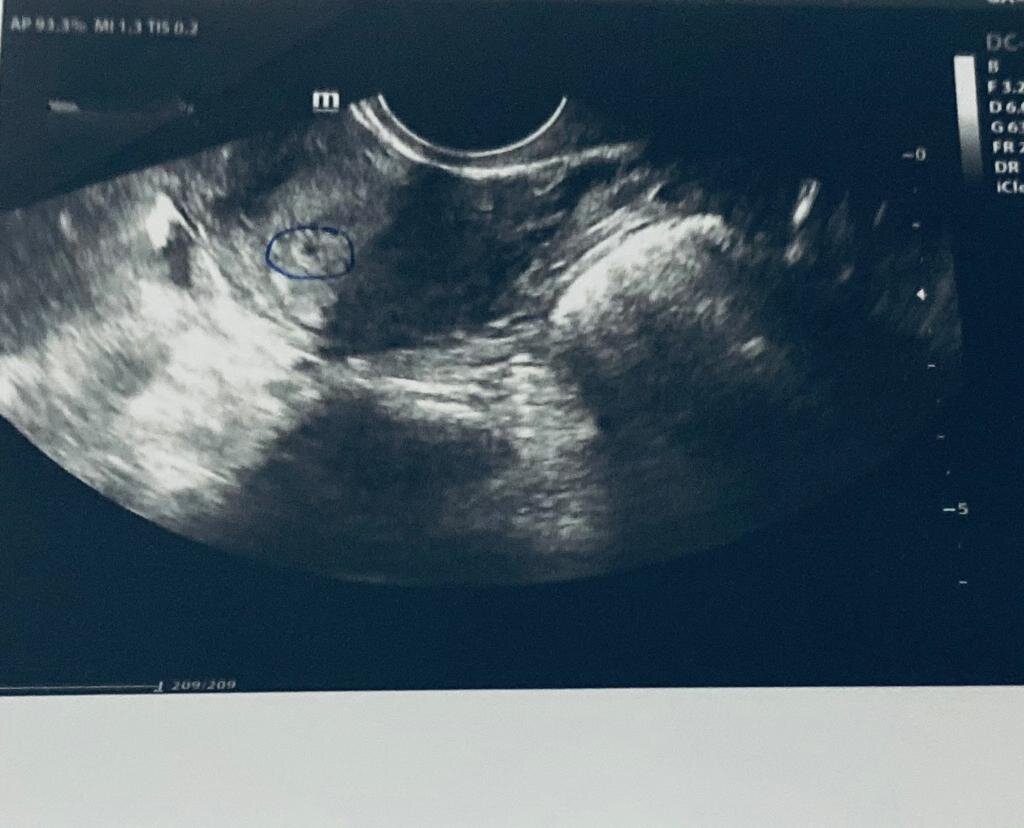

Плодное яйцо без эмбриона на раннем сроке. Может ли он появиться?

Итак, доктор подтвердил беременность. На УЗИ - еле заметная точка, "тянущая" на две недели беременности. В предыдущей статье я писала про мучения с тестом на беременность. К тому моменту уже должна была идти седьмая неделя (менструальный срок).

Никакого эмбриона и уж тем более сердцебиения при обследовании не нашли.

Никакого эмбриона и уж тем более сердцебиения при обследовании не нашли. Однако, мой гинеколог, к которому я хожу не первый год и знаю ее как грамотного специалиста, сказала, что так бывает. Вполне вероятно, что зачатие произошло позже и поэтому срок меньше.

И вот я снова в кабинете УЗИ. Специалист снова сообщает тот же неутешительный диагноз: плодное яйцо есть, а эмбриона нет. Однако, оно увеличилось в размере. Значит растет, а это, наверное, уже хорошо, решила я. Плюс появился желточный мешок.

На этот раз моё "пятно" на УЗИ уже "тянуло" на 5 недель беременности. По крайней мере так написал Насколько я к тому моменту уже успела узнать - это был хороший знак.

Там меня уже запомнили и, помню, жалобно так смотрели, когда я снова пришла. Я была заплаканная и расстроенная, уверенная, что все кончено. Но, буквально пару секунд и я услышала, как доктор просто закричала от радости:

"Вот, смотри! Эмбрион, видишь! Вот он".

Еще пара секунд и кабинет заполнил самый прекрасный звук - сердцебиение моего малыша! Буквально три дня назад ничего не было видно, а тут! Я плакала от счастья! Наконец-то я четко знала, у меня будет ребенок, я все же стану мамой! О том, что предстоят еще долгие месяцы беременности и может быть все что угодно, я тогда как-то не задумывалась. Самое главное, что сейчас все хорошо! Наконец-то!